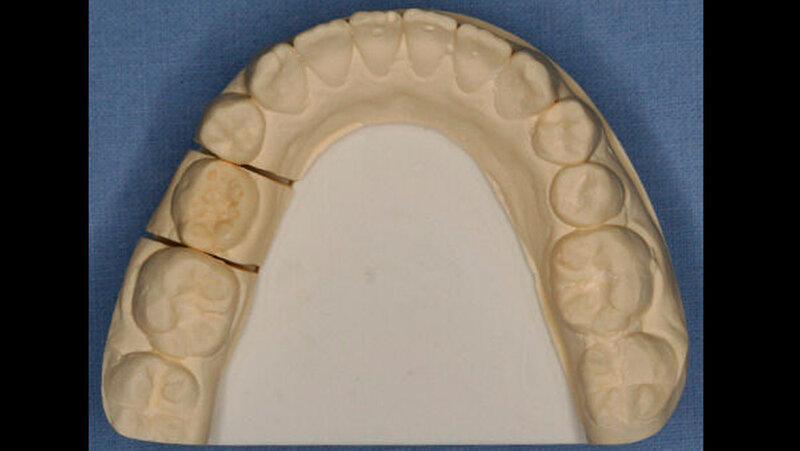

Die Patientin zeigte ein kariesfreies bleibendes Gebiss mit Nichtanlage des Zahns 35 und Persistenz des Zahns 75 auf (Abbildung 1). Sie wies im Frontzahnbereich sowie im rechten Seitenzahnbereich eine Klasse I auf, im linken Seitenzahnbereich aufgrund der Größe des Zahns 75 eine Klasse II. Zahn 75 befand sich in deutlicher Infraokklusion (Abbildung 2). Der Perkussionstest wies allerdings nicht eindeutig auf eine Ankylosierung hin.

Unmittelbar nach der Entbänderung erfolgte deshalb die Abformung beider Kiefer (Aquasil Ultra Heavy und Aquasil Ultra LV, Dentsply DeTrey) sowie eine Bissnahme im Schlussbiss (Futar Fast (1:1), Kettenbach GmbH). Im Labor erfolgte die Herstellung eines Overlays aus Komposit (SR Adoro, Ivoclar Vivadent) (Abbildungen 4 bis 6), das etwa zehn Tage nach der Abformung eingesetzt wurde.